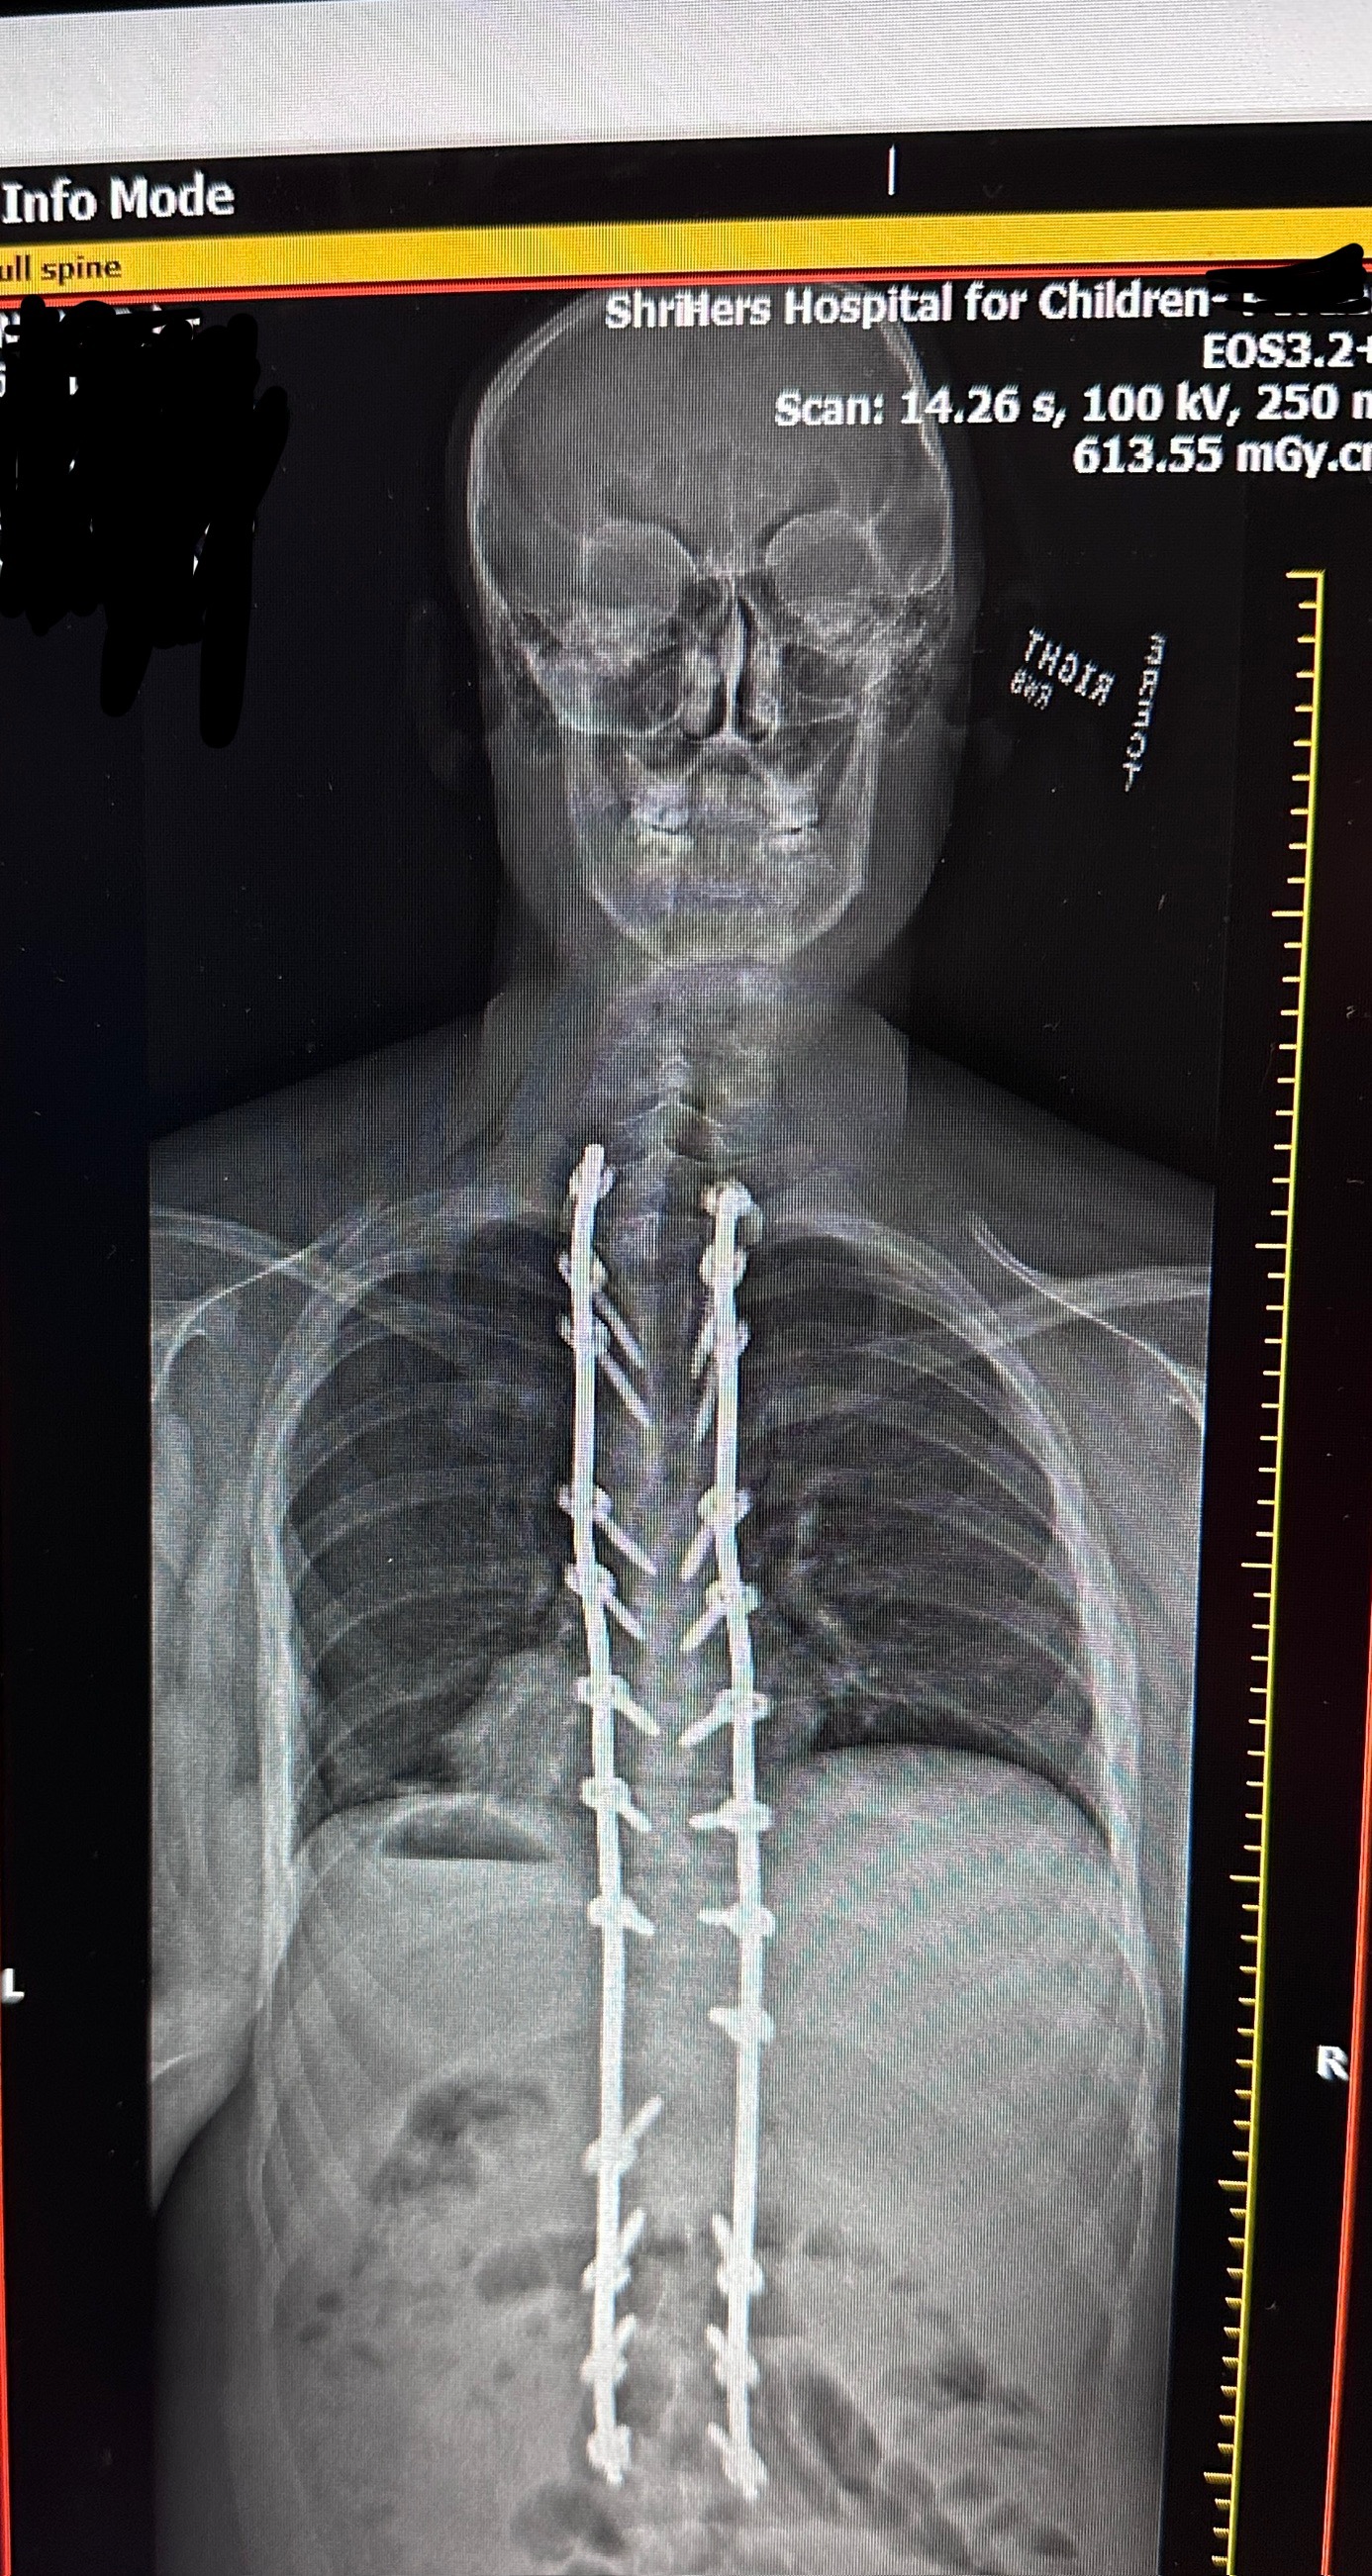

Our family has been through an unimaginable journey—one filled with fear, pain, hope, and unwavering love. Our child, Tyler, is a cancer survivor, a true warrior who has already endured more in his young life than most do in a lifetime. After bravely beating cancer, he recently underwent major back surgery—a procedure we hoped would bring relief and healing. But complications followed, and Tyler is now fighting a serious infection, resulting in an extended hospital stay and constant medical care.